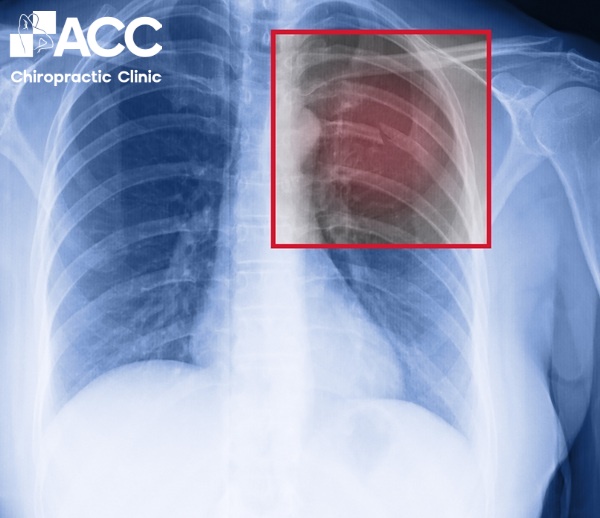

2.2 Trật xương sườn

Tai nạn, ngã, chấn thương hoặc áp lực lớn có thể khiến xương sườn bị lệch khỏi vị trí. Khi xương sườn bị trật có thể xuất hiện các cơn đau dữ dội lan sang vùng bả vai và lưng khiến bạn khó khăn trong việc vận động, một số trường hợp còn bị khó thở.